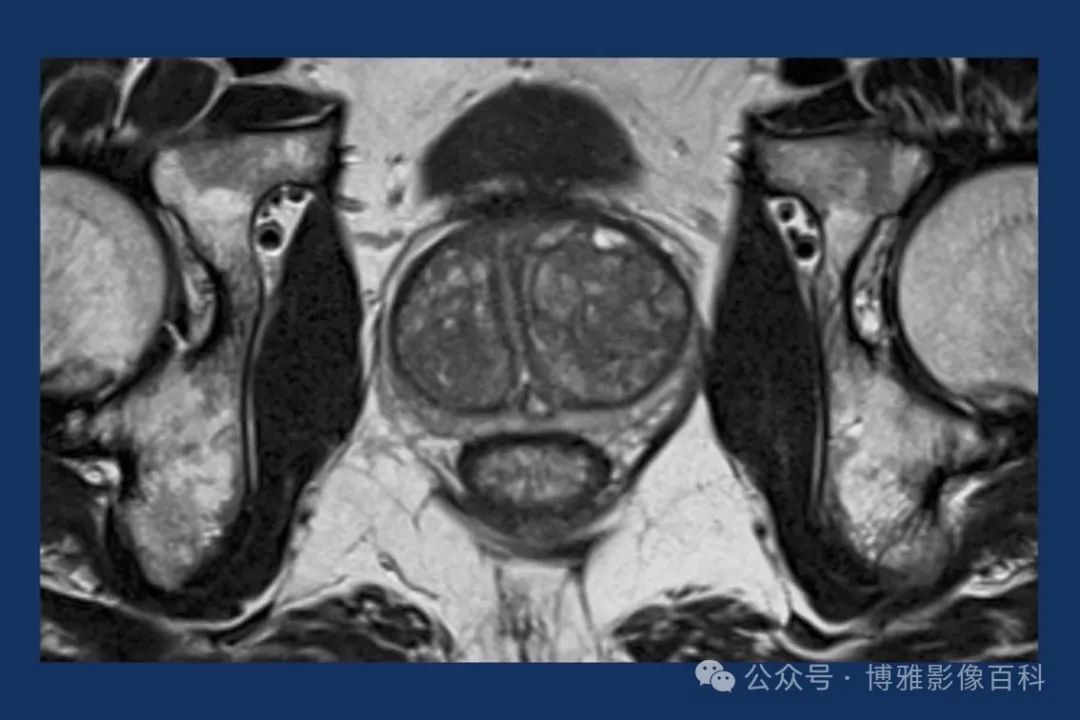

MR 解剖学

前列腺良性增生患者的轴向T2 图像,其他方面正常。外周带是一薄层均匀的高信号,边界清晰连续性的低信号包膜。移行带通常表现为不均匀中等信号,病灶被边界清楚的BPH良性前列腺增生结节所取代。精囊具有均匀T2高信号。未见淋巴结肿大。